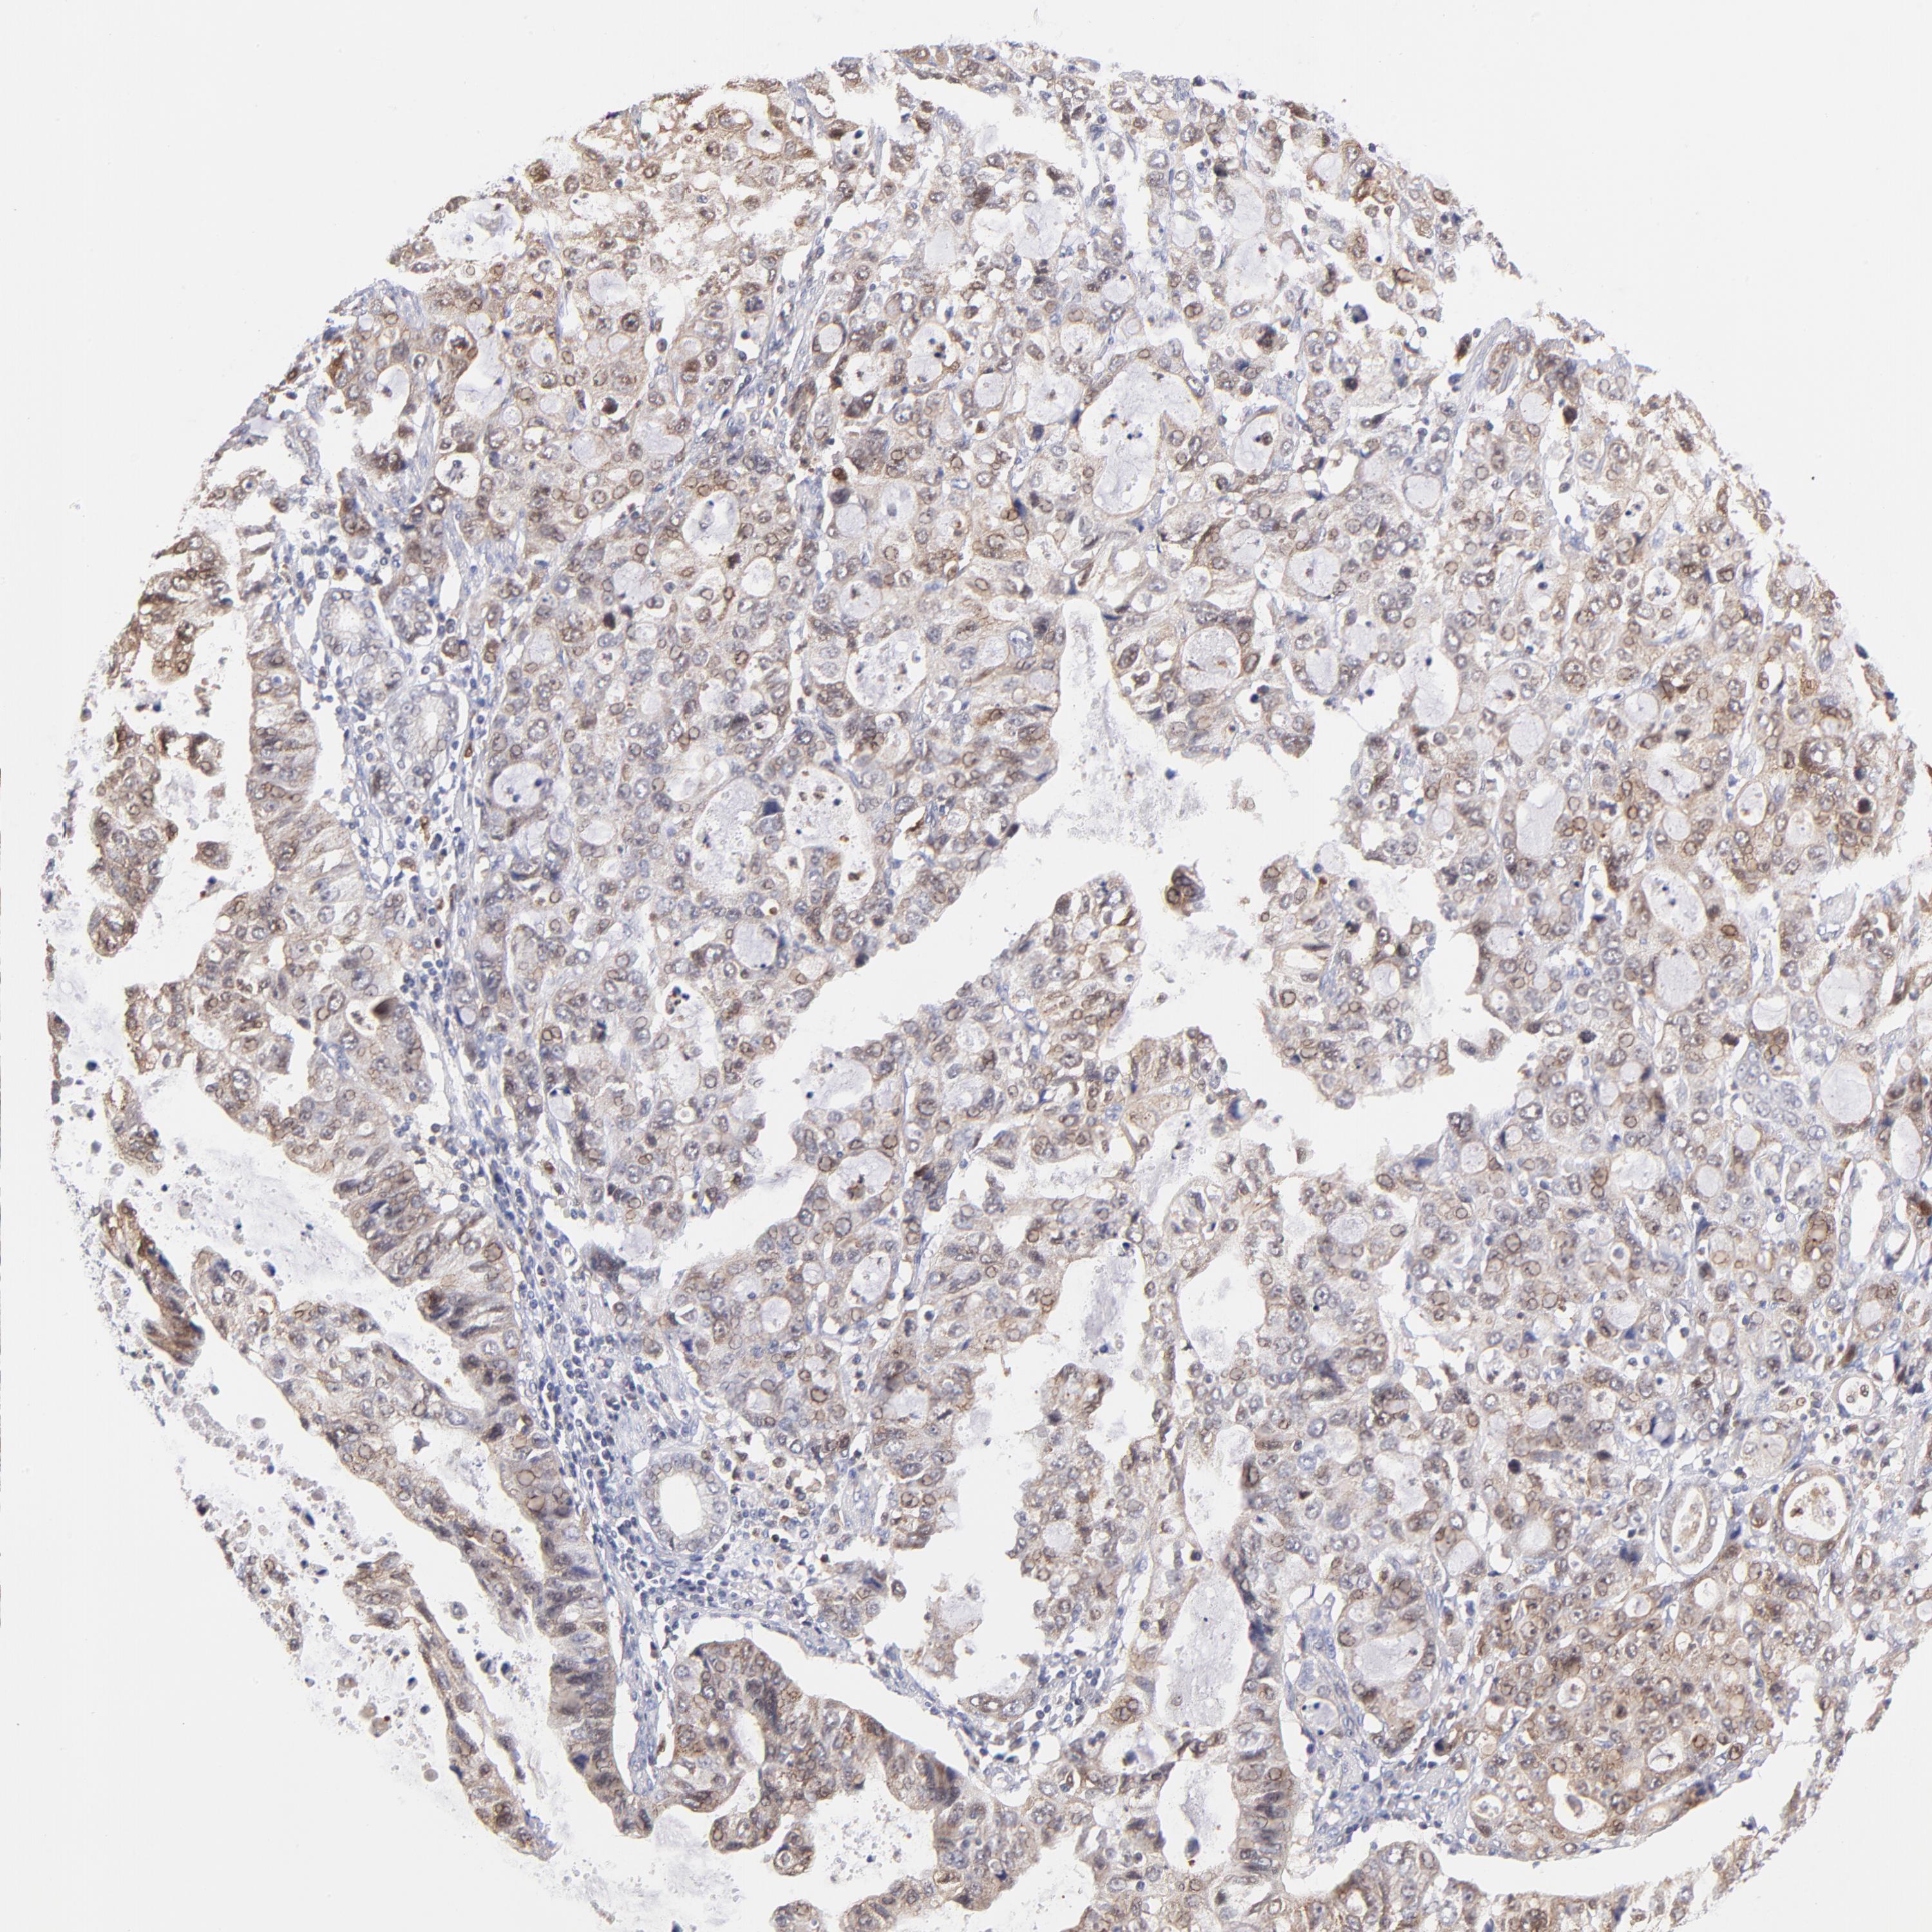

STOMACH CANCER - Protein expressioni

A mouse-over function shows sample information and annotation data. Click on an image to view it in a full screen mode. Samples can be filtered based on level of antibody staining by selecting one or several of the following categories: high, medium, low and not detected. The assay and annotation is described here.

Antibody stainingi

Antibody staining in the annotated cell types in the current human tissue is reported as not detected, low, medium, or high, based on conventional immunohistochemistry profiling in selected tissues. This score is based on the combination of the staining intensity and fraction of stained cells.

Each image is clickable and will lead to virtual microscopy that enables deeper exploration of all samples and also displays staining intensity scores, fraction scores and subcellular localization as well as patient and tissue information for each sample.

Antibody HPA000722

Antibody CAB003771

Staining

High

Medium

Low

Not detected

Intensity

Strong

Moderate

Weak

Negative

Quantity

>75%

75%-25%

<25%

None

Location

Nuclear

Cytoplasmic/membranous

Cytoplasmic/membranous,nuclear

Adenocarcinoma, NOS